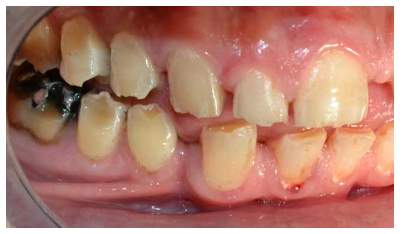

En la bibliografía se describe con detalle los defectos del esmalte que presentan los pacientes diagnosticados del síndrome de Morquio. Estos defectos son una característica aparentemente constante en la enfermedad y, por lo tanto, hace necesaria las visitas al odontólogo para su control evitándose problemas mayores. Dichos defectos consisten en un esmalte anormalmente delgado, que es áspero debido a los numerosos hoyos diminutos y a una superficie irregular. La delgadez del esmalte da como resultado una forma alterada y decoloración de los dientes que, añadido a los diastemas interdentales, provocan alteraciones en la oclusión. Aparte de estos defectos, el esmalte es histológicamente normal y tiene una dureza y radiodensidad normales. El tratamiento odontológico de los pacientes con MPS-IV requiere colaboración multidisciplinar, debido a que las manifestaciones orales de la enfermedad pueden aparecer a cualquier edad, resultando en ocasiones tedioso para el paciente y complicado para el profesional. Especial mención merecen las terapias utilizadas como tratamiento sintomático de la enfermedad, así como el manejo de la vía aérea en el caso de intervenciones bajo anestesia general o sedación para tratar ciertas patologías del territorio bucomaxilodental.

The enamel defects presented by patients diagnosed with Morquio syndrome are described in detail in the bibliography. These defects are an apparently constant feature in the disease and, therefore, make visits to the dentist necessary for their control, avoiding major problems. These defects consist of an abnormally thin enamel that is rough due to numerous tiny holes and an irregular surface. The thinness of the enamel results in an altered form and discoloration of the teeth, which added to the interdental diastemas, cause alterations in the occlusion. Apart from these defects, the enamel is histologically normal and has a normal hardness and radiodensity.

- A nivel dentario, el esmalte es uniformemente anormal, delgado, rugoso e hipoplásico. Afecta a ambas denticiones, y provocando una marcada frecuencia de fracturas dentarias, desgastes o abrasiones y caries. Existe un importante componente lingual en maloclusión, diastemas en toda la arcada y prognatismo mandibular, así como bruxismo y patología de ATM. Incisivos con forma de pala y molares cóncavos que favorece las lesiones de caries y sensibilidad dentinaria.

Los pacientes con síndrome de Morquio, a menudo, necesitan tratamiento de ortodoncia para la corrección de la maloclusión, lo que a su vez mejora la función masticatoria. Se podrían corregir las inclinaciones labiales de los dientes anteriores superiores e inferiores y se cerrarían los espacios interdentales para una correcta higiene, evitándose así la aparición de caries37.

Estos pacientes muestran arcos maxilares y mandibulares espaciados con un hábito de empuje lingual a la vez que también suelen presentar un labio superior sobresaliente, inclinación labial de los dientes anteriores superiores e inferiores y esmalte delgado. El hábito de empuje de la lengua suele desaparecer después de la aplicación de un aparato de ortodoncia removible. La dentición espaciada en los arcos superior e inferior mejora después del tratamiento con un dispositivo fijo con cable de arco de bucle de cierre (0.017 x 0.025) y bandas en los molares superiores e inferiores, sin utilizar dispositivos de borde debido a la fragilidad y mala calidad del esmalte38.